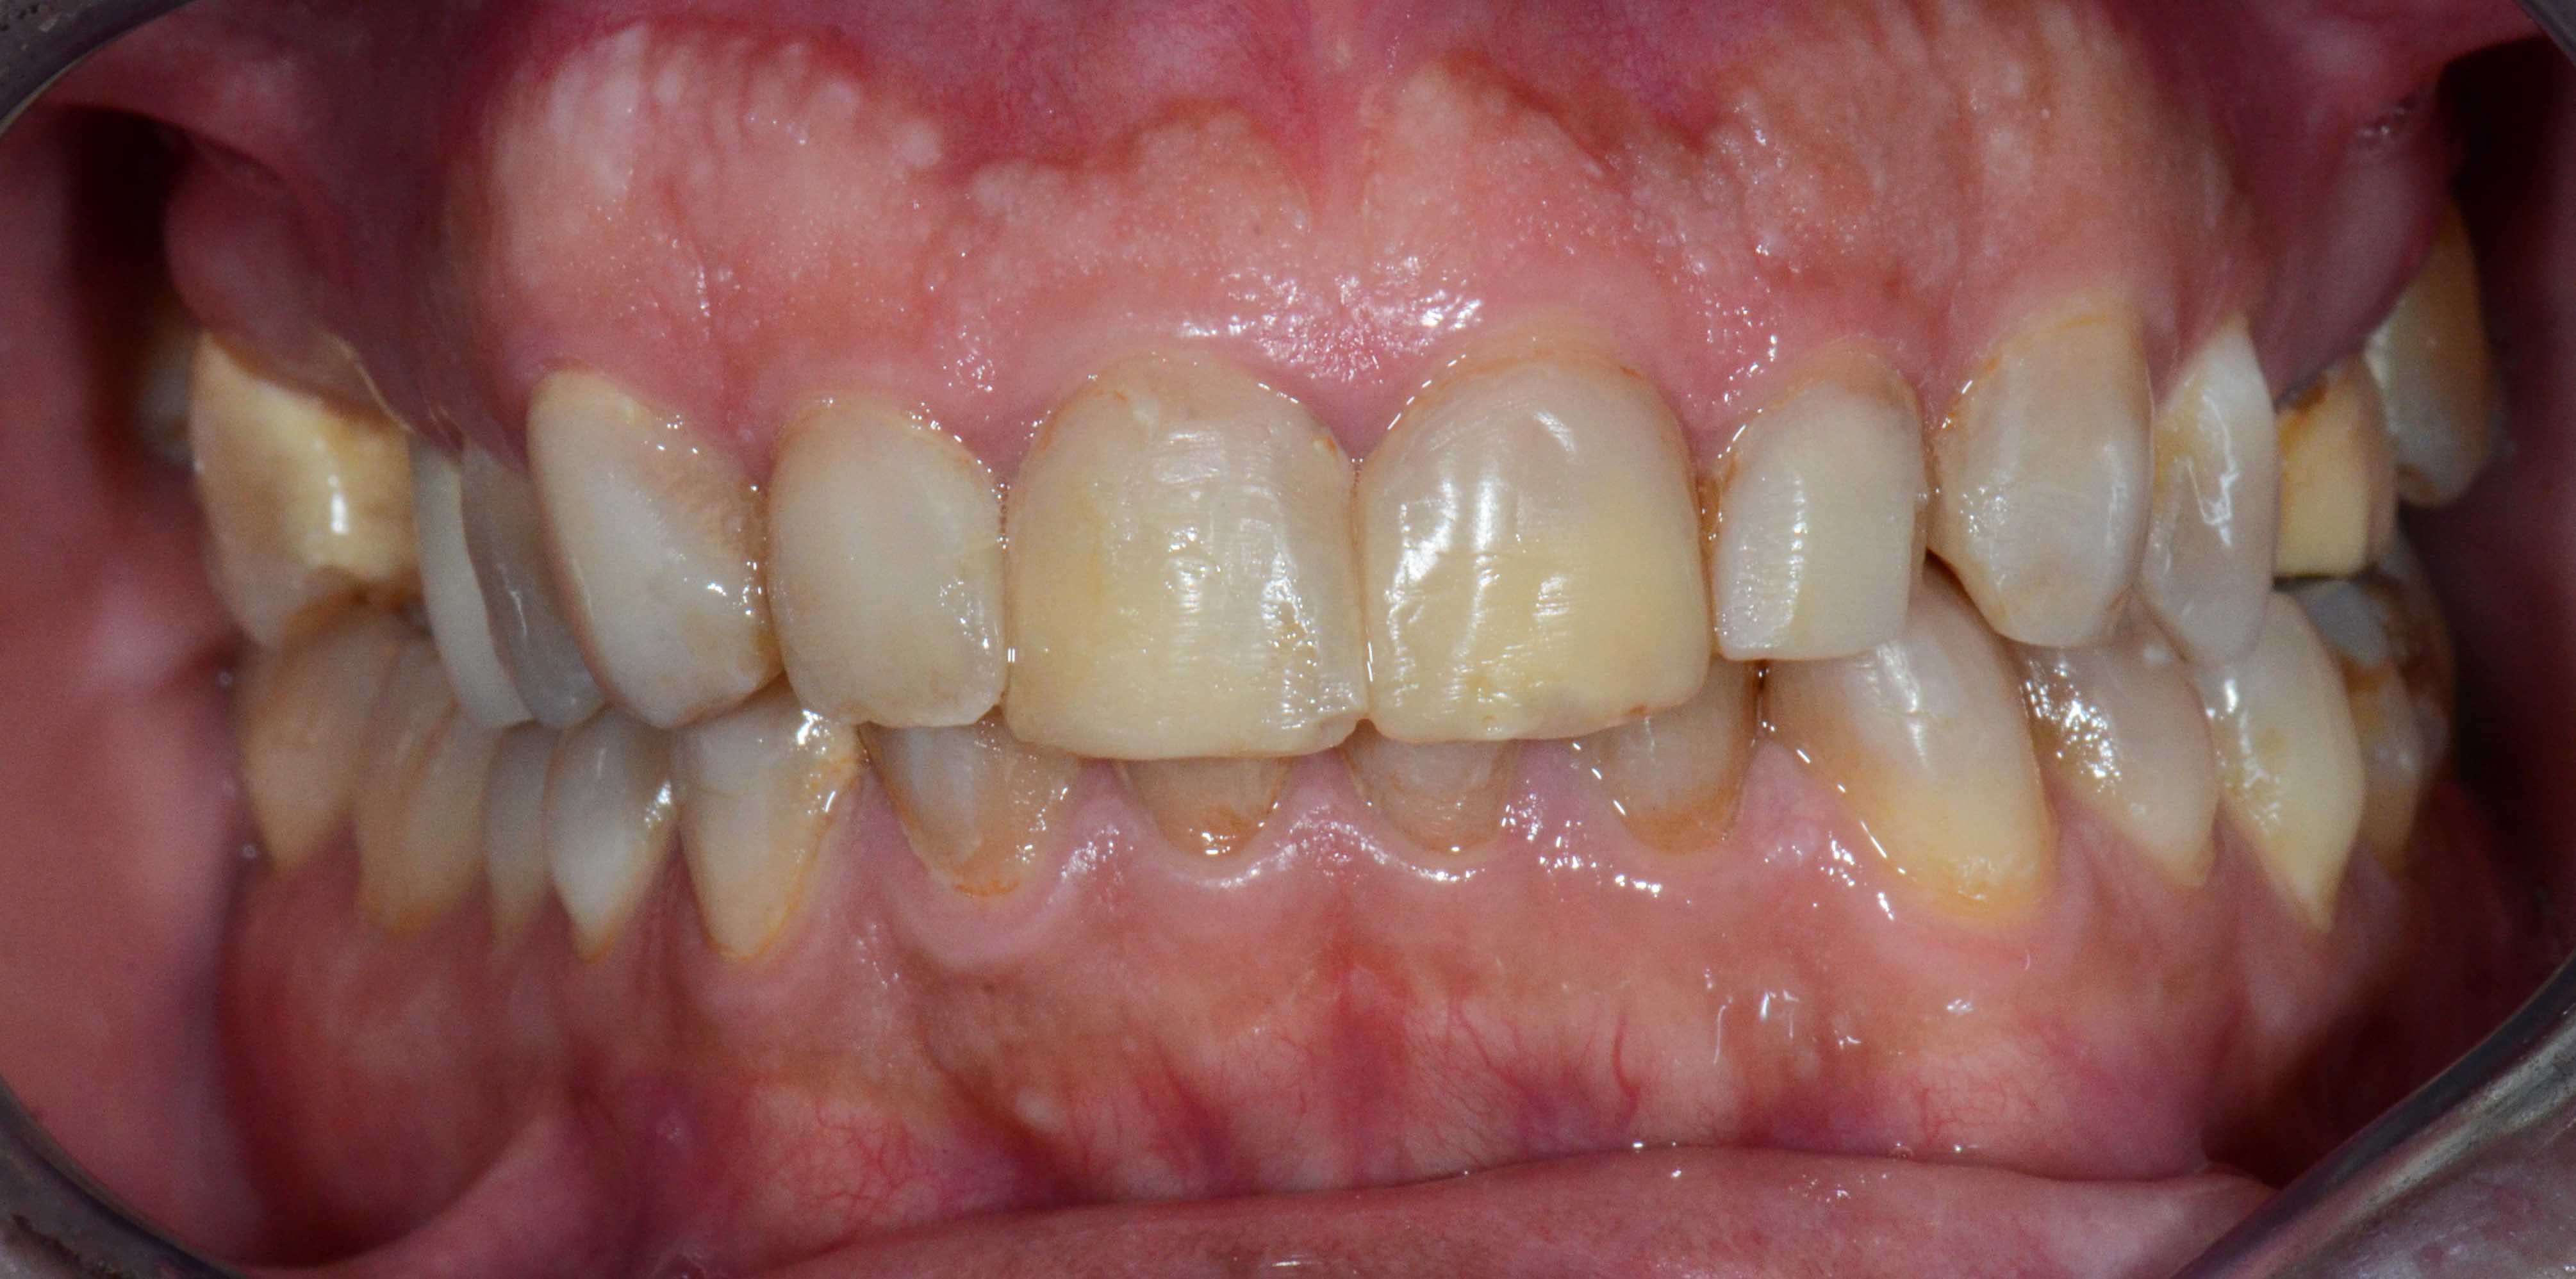

Patient with limited functions and serious aesthetics problems.

Complex Rehabilitation – The Treatment:

The natural teeth that had a good prognosis were kept and the ones that needed their position changed were moved by a fixed orthodontic brace.

Afterward a surgery was made to place some implants. The treatment was finalized by placing the ceramic crowns over the implants and teeth.